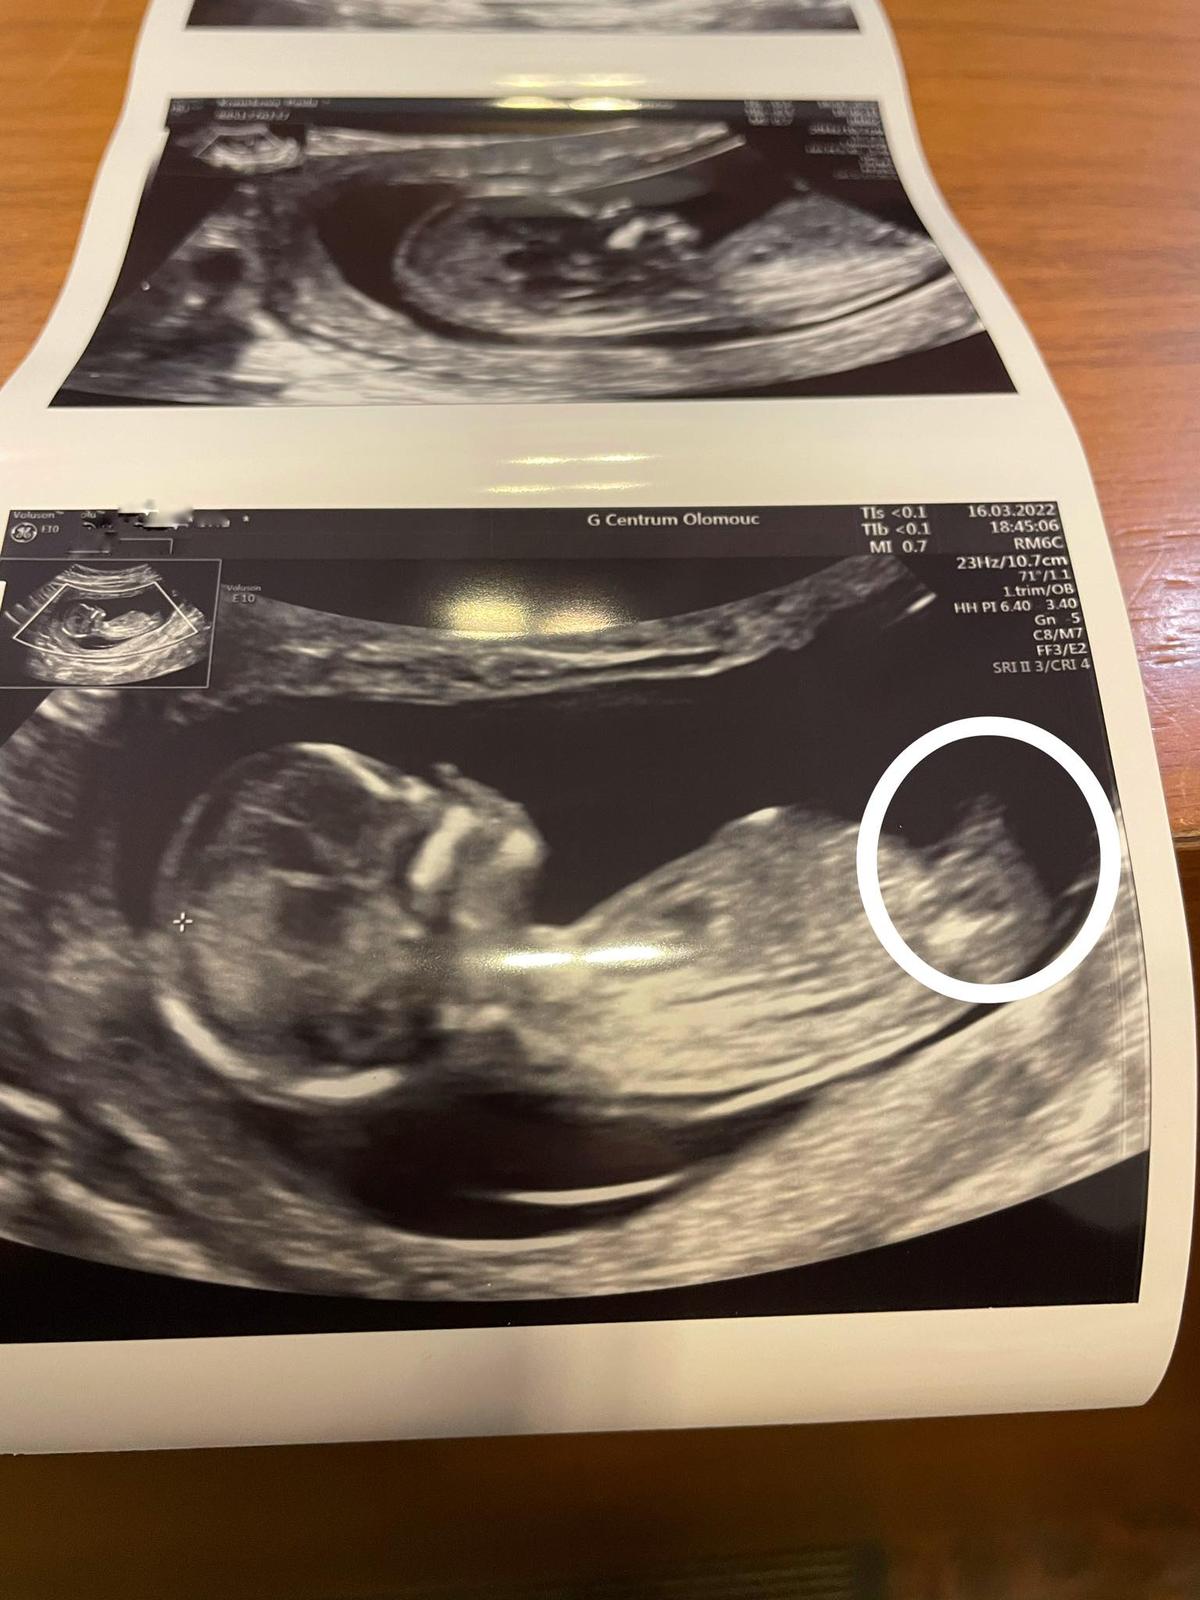

Pohlaví. Holčičku už nejspíš můžeme vyloučit, že ano?

podle další kontroly na 1. screeningu se jedná podle paní doktorky na 99 % o chlapečka, i když to vypadalo na předchozí kontrole na holčičku, viz první dotaz 🙂 https://www.modrykonik.cz/ask-an-expert/poradna...

Holčičku už nejspíš můžeme vyloučit, že ano? 🙂

jak už jsem několikrát psal, z jednoho snímku se velmi obtížně posuzuje a snímek, co přikládáte, není úplně optimální, nic nenahradí live vyšetření. Nicméně, asi bych se stejně stále držel toho, co jsem psal minule. 🙂

A stále také platí - před nákupy vyčkejte na potvrzení v II. trimestru. 😉